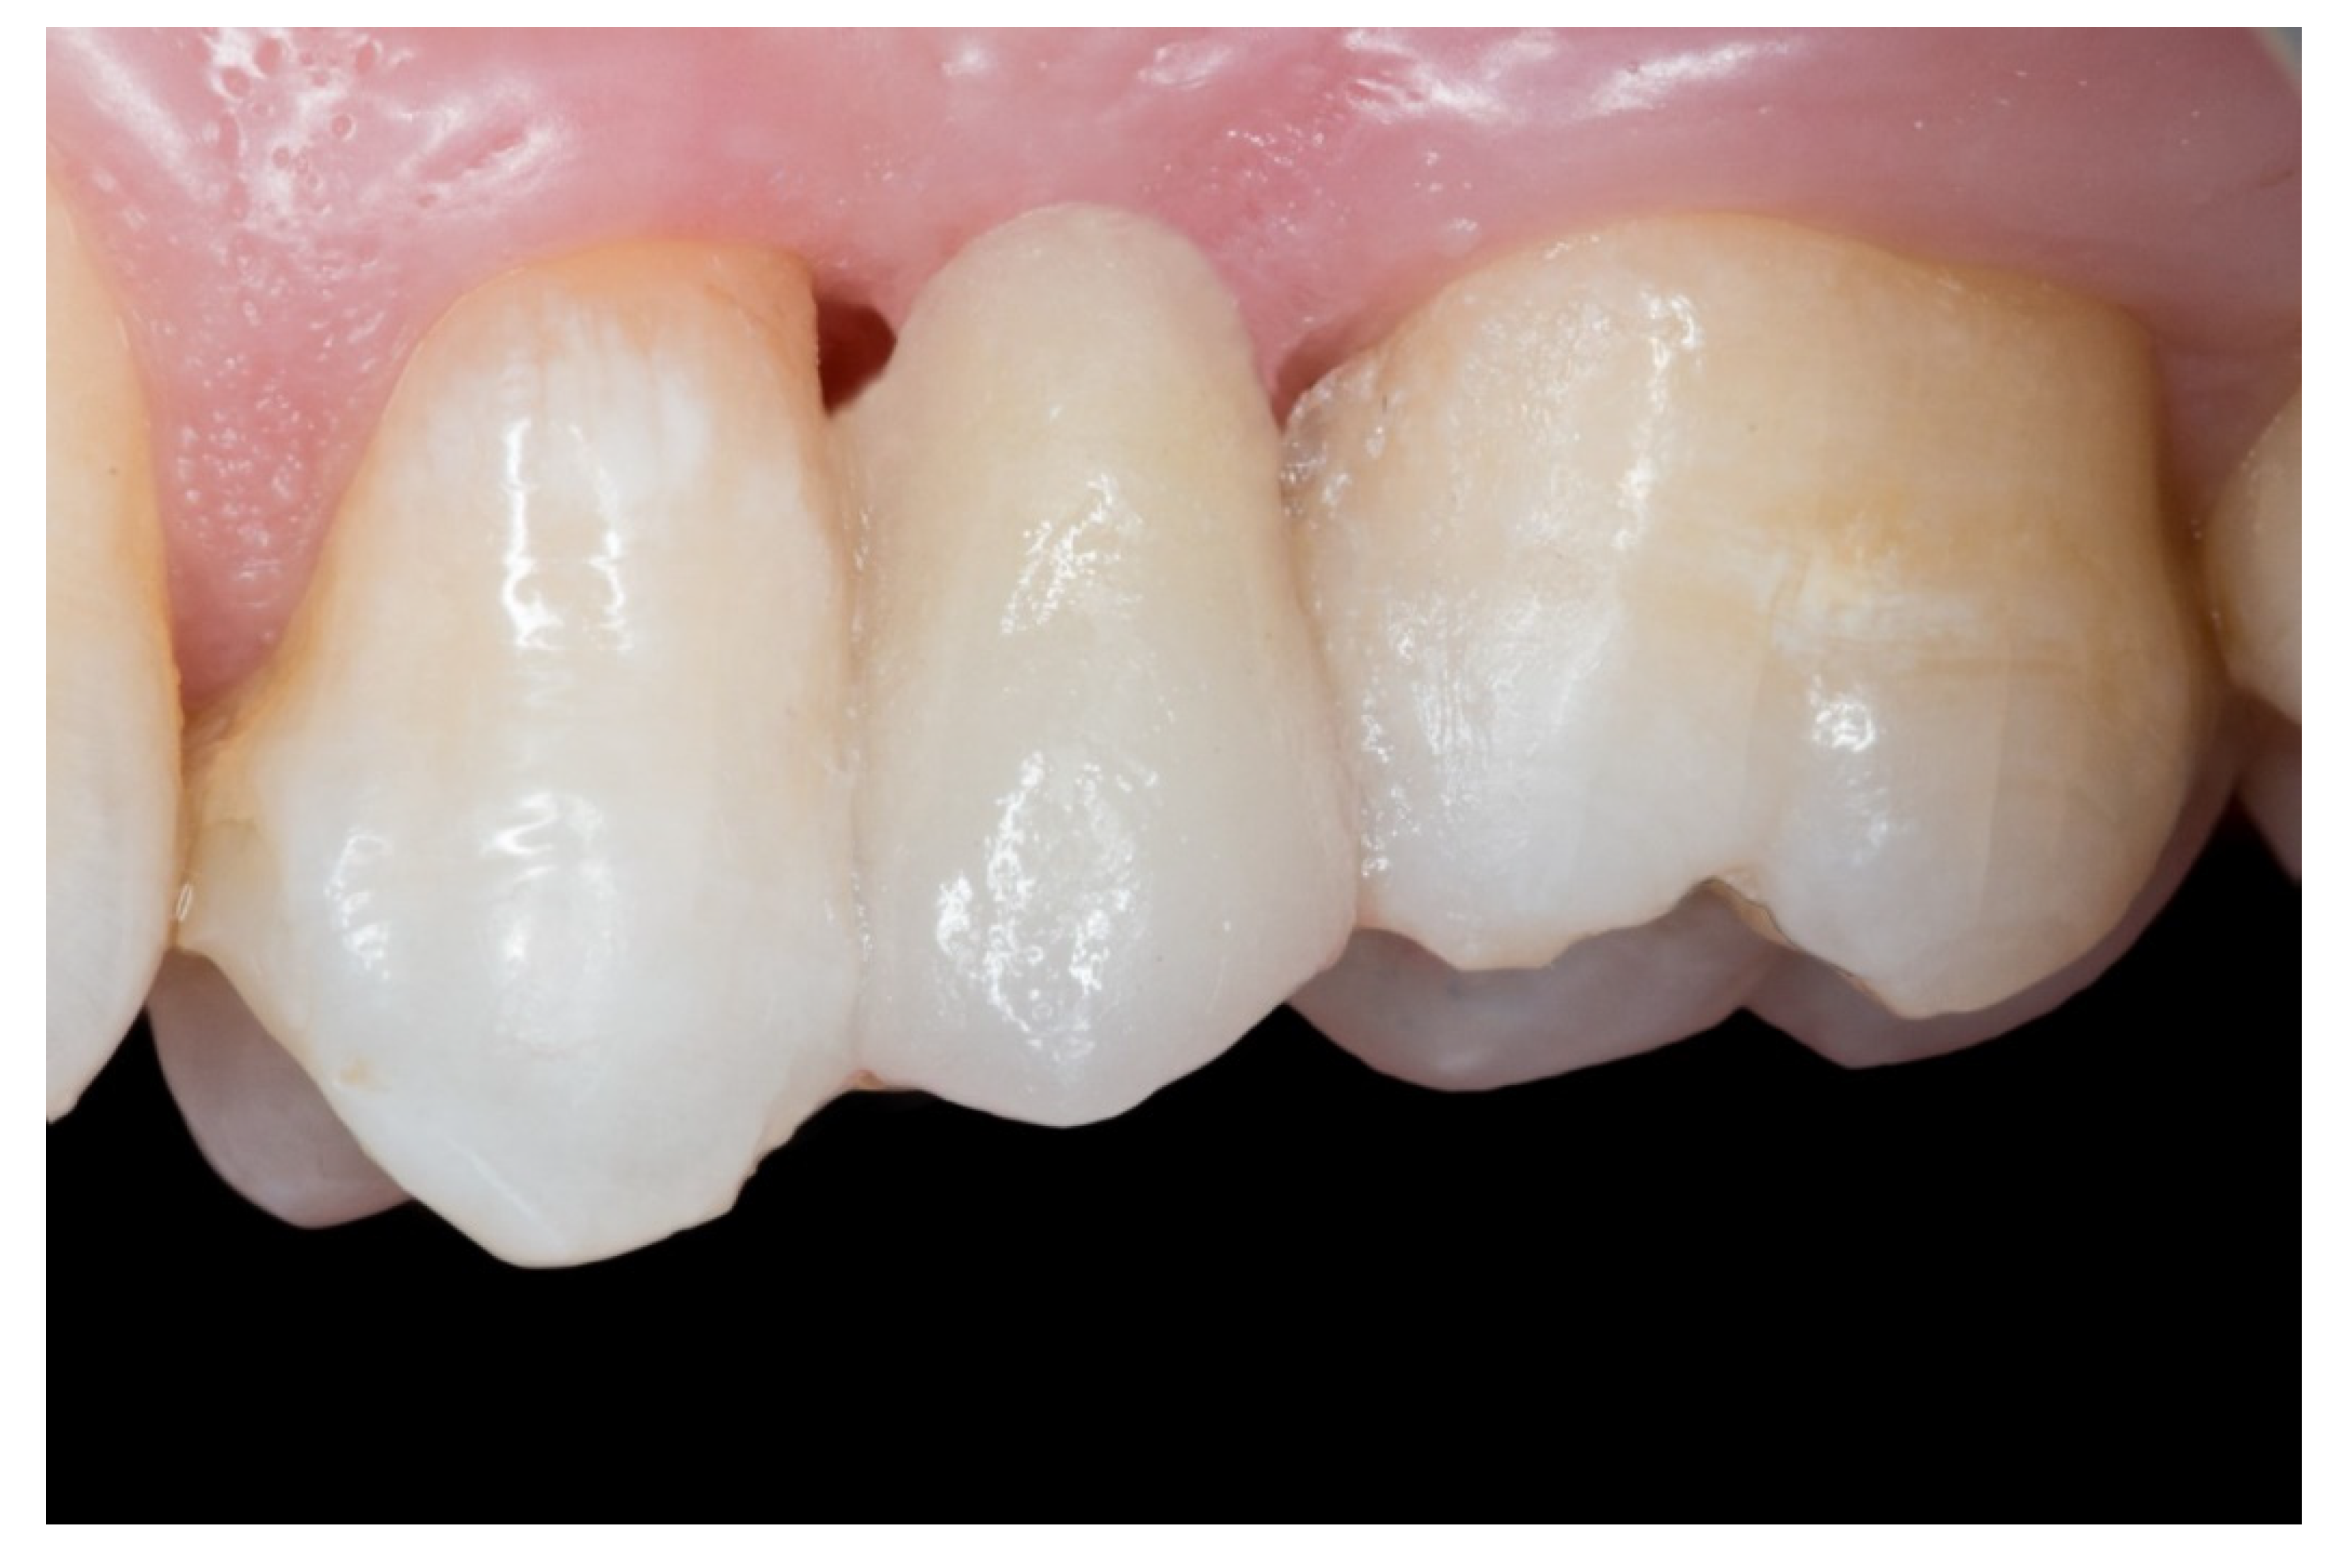

Figure 7.

The FRCB after the occlusal adjustment and composite polishing.

6. Finally, when the FRCB were complete, the occlusion was checked, premature contacts were relieved and the restorations were polished with a composite finishing and polishing kit (Figure 7).